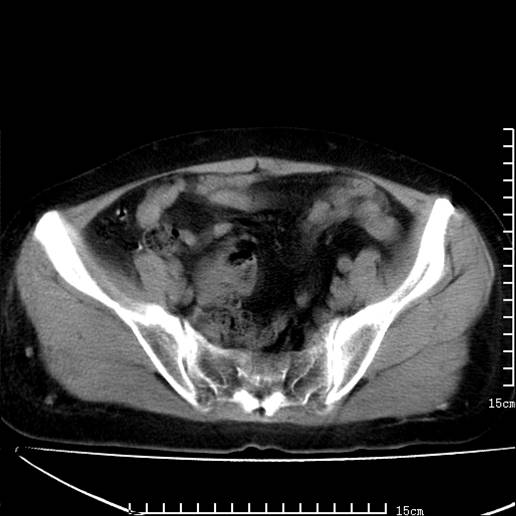

以下是引用pujunzhi在2008-5-30 15:31:00的发言:[br]异位肾—盆腔肾。当看到肾窝无肾脏时,要想到孤立肾和异位肾,异位肾最常见是盆腔肾,偶见胸腔,易误认为肺占位,只要想到就不会漏诊。建议增强扫描。